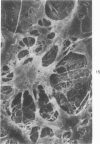

Common biliary ducts of 32 adult mongrel dogs were ligated for a period of 2 days to 6 weeks. Sham-operated animals served as controls. Bile ducts were removed at sacrifice, and biophysical, morphologic, and biochemical parameters were measured. Our study shows that biliary duct ligation results in an immediate increase of intraductular pressure and is followed quickly by significant increase in the rate of collagen synthesis and the activity of prolyl hydroxylase. Histologic data show subepithelial inflammation followed by marked increases in periductular fibrosis. This fibroproliferative response is paralleled by peak levels of prolyl hydroxylase activity at 2 weeks prostligation. Paradoxically, bile ducts continuously distend throughout the ligation period despite increased fibroplasia. We present here the first topographic (SEM) study of normal and ligated common bile duct epithelium. Following 2 weeks of ligation large crater-like fenestrae are seen ductular epithelial surfaces. This is followed by focal epithelial sloughing. We speculate that the continuous distention and epithelial necrosis seen in the present study may be due to biliary stasis and/or subepithelial infiltration of bile through epithelial fenestrae. This hypothesis is supported by our studies which show that collagen extractibility is markedly increased by the addition of bile to the homogenate.